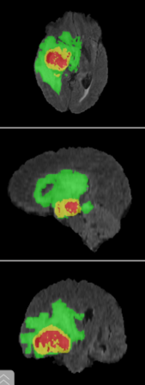

Fokus der Anwendung ist, eine hochpräzise dreidimensionale Segmentierung von bösartigen Hirntumoren, wie Glioblastomen, durchzuführen.

Dafür haben die Wissenschaftlerinnen und Wissenschaftler aus dem Forschungsbereich Künstliche Intelligenz in der medizinischen Bildverarbeitung ein U-Net, ein leistungsstarkes neuronales Netzwerk, trainiert. Da es sich dabei um ein überwachtes Lernverfahren handelt, wird im Training mit MRT-Bilddaten gearbeitet, die bereits Expertensegmentierungen enthalten.

Nach erfolgreichem Training wird das optimierte neuronale Netzwerk in die interaktive Anwendung integriert, die dann in der Lage ist, neue, zuvor nicht bekannte MRT-Bilddaten zu segmentieren und auszuwerten.